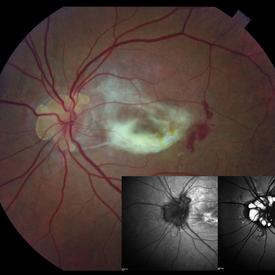

Angioid Streaks With Associated Disc Drusen and CNV

Sep 21 2018 by Sarah Oelrich

Angioid streaks with associated disc drusen and CNV.

Photographer: Sarah Oelrich CRA COT, Southeastern Retina Associates Knoxville Tn

Condition/keywords: angioid streaks, autofluorescence imaging, choroidal neovascularization (CNV), disc drusen, infrared image